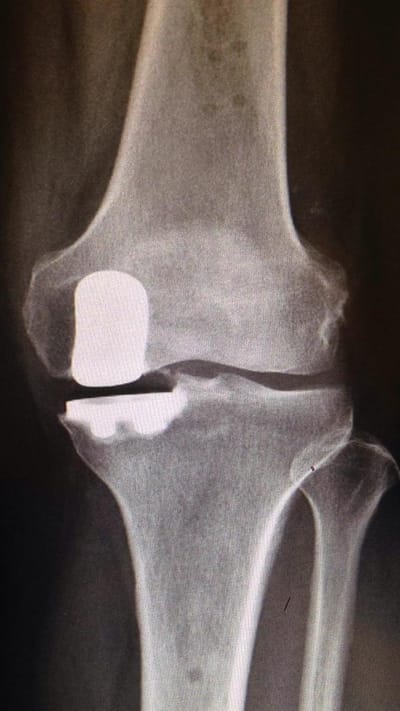

La protesi rappresenta una sostituzione della superficie articolare usurata. Di fatto le moderne protesi possono essere considerate dei rivestimenti della superficie articolare.

Vi sono diversi tipi di gonartrosi pertanto vi sono diverse soluzioni protesiche: monocompartimentali (mediale, laterale, femororotulea), totali (bicompartimentali, tricompartimentali) con conservazione del legamento crociato posteriore, con conservazione del legamento crociato anteriore, posterostabilizzate, e da revisione.

Nelle radiografie qui sotto si nota come in quella di dx vi è lo spostamento dello stelo femorale rispetto quella di sx: ciò sta ad indicare la mobilizzazione dell’impianto a livello della componete femorale.

A seguire il risultato radiologico della revisione.